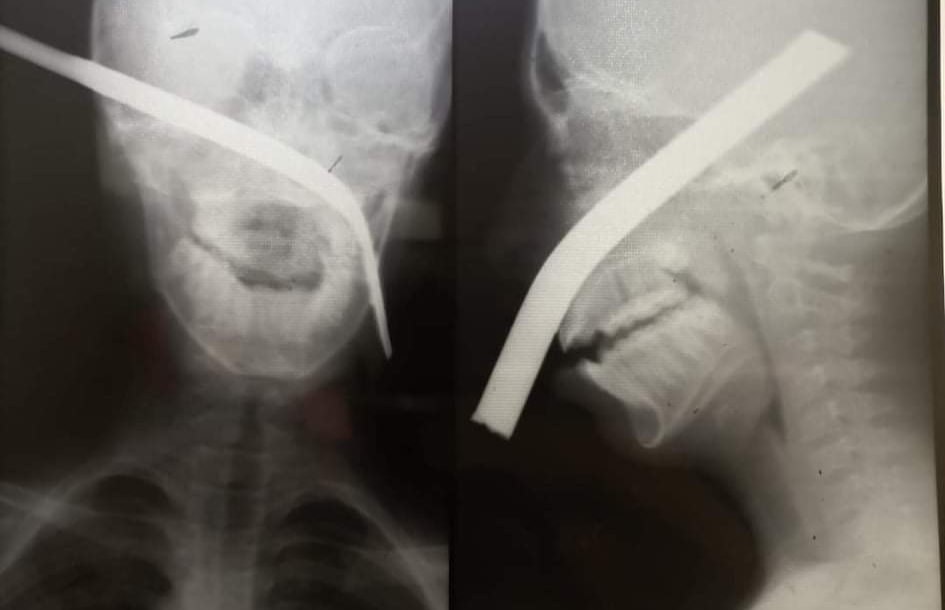

استخراج سيخ حديد من وجه طفل بالمنيا

نجح أطباء مستشفى المنيا الجامعي، في استخراج سيخ حديد من وجه طفل صغير، وخرج جزء منه من جانب عينه اليسرى، حيث تعد العملية من العمليات الصعبة والنادرة.